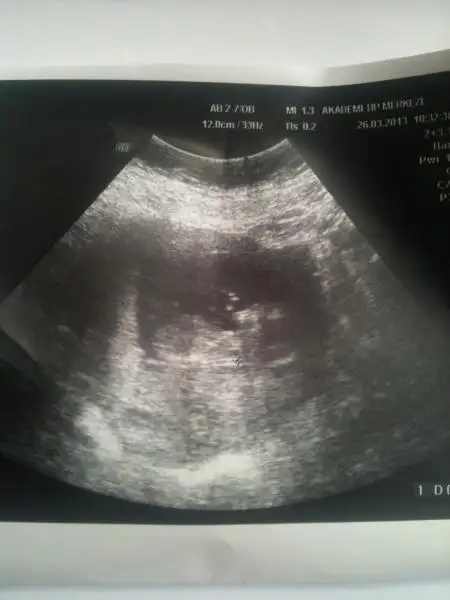

KIZLAR BUDA BENİM BEBİŞİMİN 16+5 HAFTALIK SON RESMİ :nazar:

$Resim 025.webp

e bana kımse yorum yapmamış:ssz: orkıdem...yada anlayan arkadaşlar.... ben bu teorıden anlamadımda